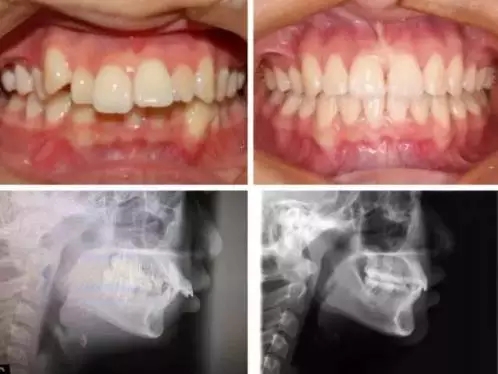

当然,每个个体的生理情况不一样,牙齿的移动速度不同,矫正时间也会不同,另外有一种情况必要要了解,骨性的矫正,尤其是骨性龅牙,因为牙槽骨非常致密,改建过程较困难,所以矫正时间相对要增加,通常会超过2年甚至更长。

牙齿矫正是一项系统工程,不是一朝一夕就可以完成的,患者一定要赋予更多的耐心和恒心,才能收到更加良好的矫治效果。